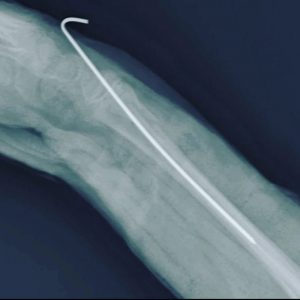

- Fracturas de codo

- Fractura supracondílea

Fractura supracondílea de humero

Fractura radiocubital

Fractura de radio distal